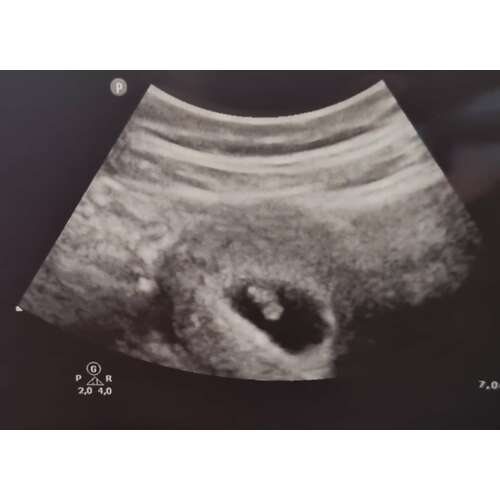

Bij mij was mijn vruchtzakje ook helemaal niet mooi rond. De gynaecoloog heeft hier ook nooit iets van gezegd. Intussen is ze al bijna 5 maandjes oud🥰

Als ik naar al mij 4 keer de zwangerschappen en echo's heb gekeken rond de 6 weken was het bij mij ook allemaal hobbelig en niet mooi rond. 1 van alle is esn miskraam geworden maar dat konden ze niet zien aan de vorm ik heb het ook echt nog nooit gehoord... de volgende echo's werden ze al wat mooier rond... maar hun hebben ervoor gestudeerd... wanneer mag je terug?

Hoi allen, hoe is het uiteindelijk bij jullie allemaal verlopen? Wij hadden gister onze eerste echo (ongeveer 6.3 wk) en onze Vk was ook wat voorzichtig met goed nieuws brengen door de vorm van de vruchtzak. Echter wel een hartslag; langzaam maar dit hoeft nog niets te betekenen met dit termijn.